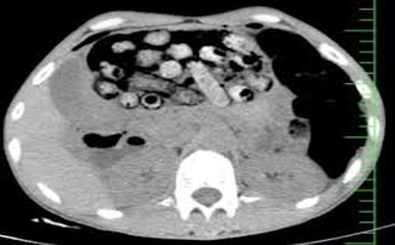

دانشگاه علوم پزشکی البرز از خارج کردن ۹۰ بسته مواد مخدر از معده و روده یک بیمار در کرج خبر داد.